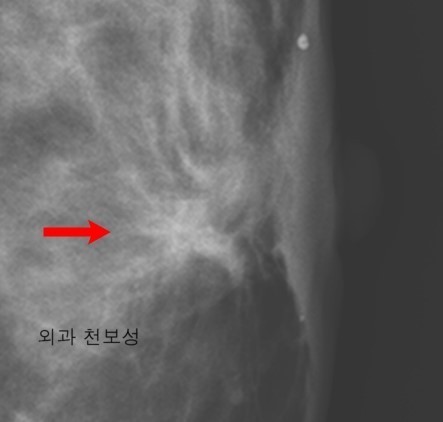

유방암 초기증상 - 유방 피부의 함몰 (보조개 현상)

- 설명: 유방암 세포가 유방 내부의 인대 조직을 침범하여 끌어당기면, 암이 위치한 부위의 유방 피부가 안쪽으로 움푹 들어가 마치 보조개처럼 패인 형태를 보이게 됩니다. 이 현상은 팔을 들거나 자세를 바꿀 때 더욱 뚜렷하게 관찰될 수 있으며, 암이 상당 부분 진행되었음을 시사하는 중요한 신호입니다.